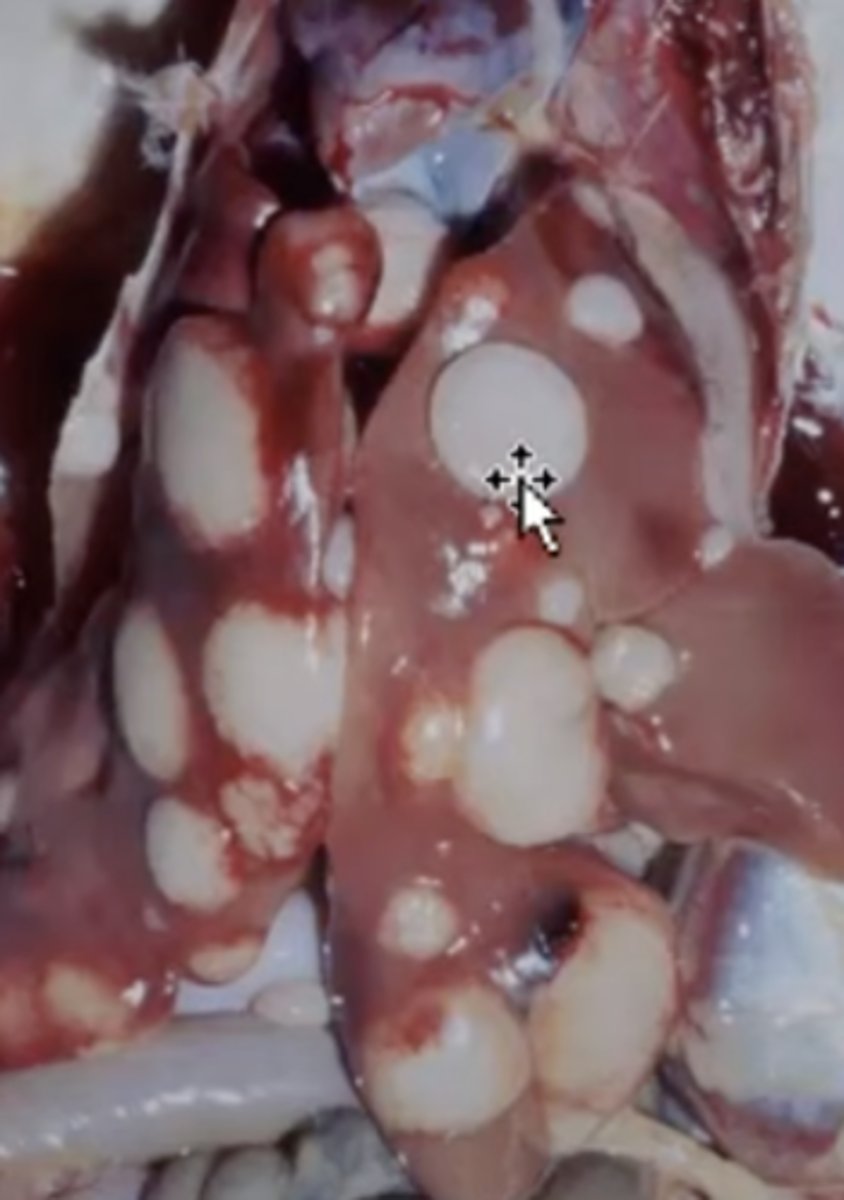

Hepatocellular carcinoma

-firm tissue

-malignant

-

What has caused this gross appearance of this liver?